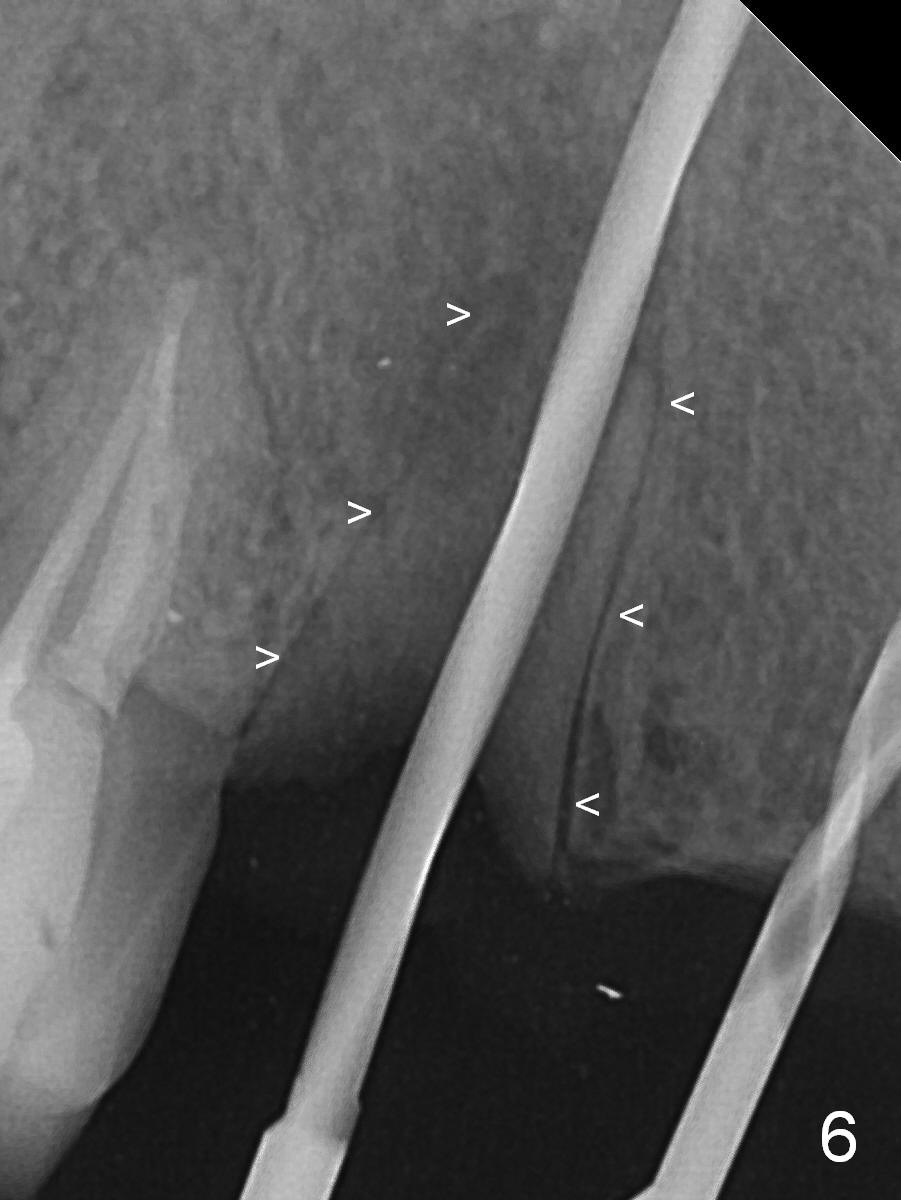

When the bridge is sectioned between #7 and 8, the tooth #6 is found non-salvageable (Fig.1).  Incision shows the atrophic buccal plate at #7 (Fig.2 arrowheads); to prevent the same feature from happening at #6 with thin buccal plate, the most buccal portion of the root is preserved (socket shield (Fig.2-4: *)).  The initial osteotomy is established in the palatal slope at #6 (Fig.5 circle) with 1.5 mm drill (Fig.6,7).  A portion of the root is visible in Fig.6 (arrowheads).  After sequential osteotomy with 2 mm, 3 mm (Fig.8) and 3.2 mm drills, a 4x15 mm implant is placed (Fig.10).  To accommodate the cross bite, the coronal portion of the implant (Fig.9 white circle) is positioned close to the socket shield.  It appears that the shield prevents the implant from encroaching the buccal plate.